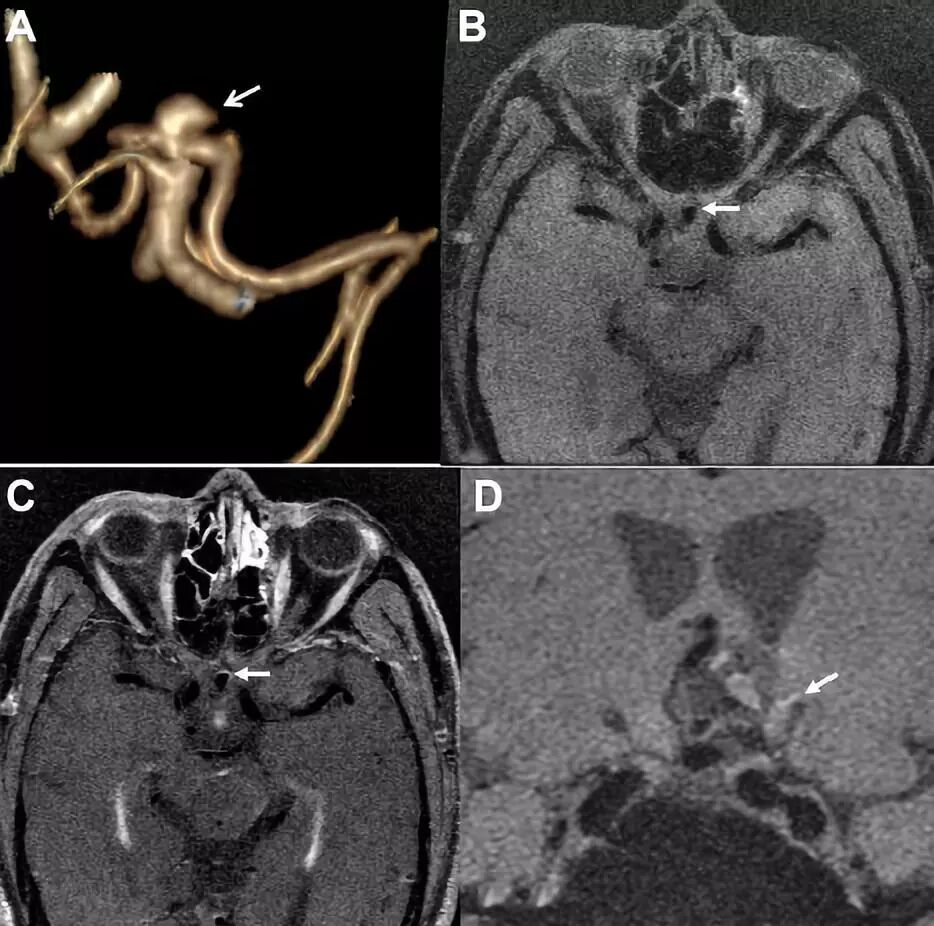

图3.前交通动脉瘤,CTA 3D图像显示形态不规则(A),与增强前(B)相比,增强后可见瘤壁部分增强(C),19天后,动脉瘤破裂出血(D)。

有研究报道,动脉瘤瘤壁增强在多发动脉瘤合并蛛网膜下腔出血时是有帮助的,可能提示破裂点。本研究中有6例部分增强位置与HRMRI或术中确认的破裂点吻合。研究中1例部分瘤壁增强的未破裂动脉瘤,在19天后出现破裂。因此,动脉瘤的部分瘤壁增强可能预示破裂点,对临床医生有价值。